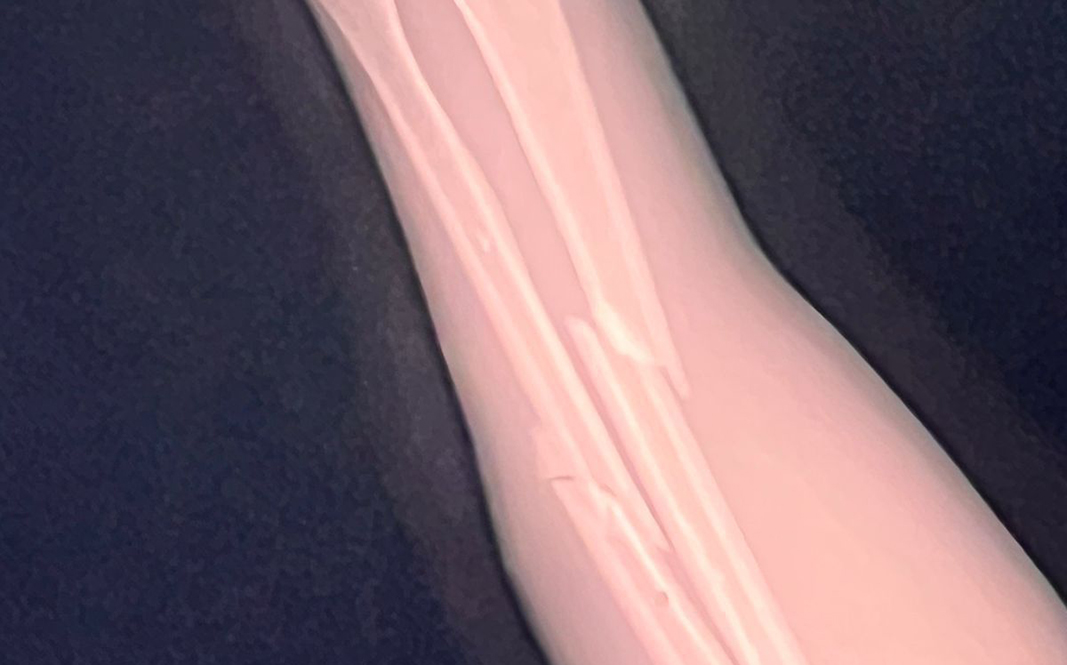

En su intento de evitar la detención el hombre empujó al oficial haciéndolo caer sobre su brazo izquierdo lo que causó fractura de radio y cúbito; el hombre fue intervenido y detenido por otro uniformado de la Policía Municipal presente en el lugar.